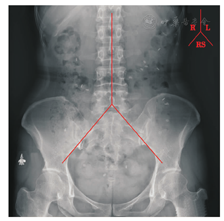

嘱患者于检查前3 d停用泻剂及影响胃肠运动的药物和食物,检查期间保持正常生活及饮食习惯,记录每一次的排便次数和时间。检查当日晨起早饭后吞服1粒胃肠动力标记物胶囊(北京镜缘博通医疗器械有限公司,每粒胶囊含24枚硫酸钡钡环),应用简易法于48 h后行腹部立位平片[11]。按照Arhan的读片方法[12]:从第12胸椎棘突至第5腰椎棘突作连线(腹中线),再从第5腰椎棘突向骨盆出口两侧做切线,将结肠分为左半结肠区(L),右半结肠区(R)和直肠乙状结肠区(RS)3个区域,通过对这3个区域标记物分布情况,进一步明确功能性便秘的分型(图1)。